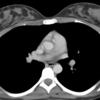

Aortic nipple

Ex 1 CT

Date: 03/23/2004

Views: 5583